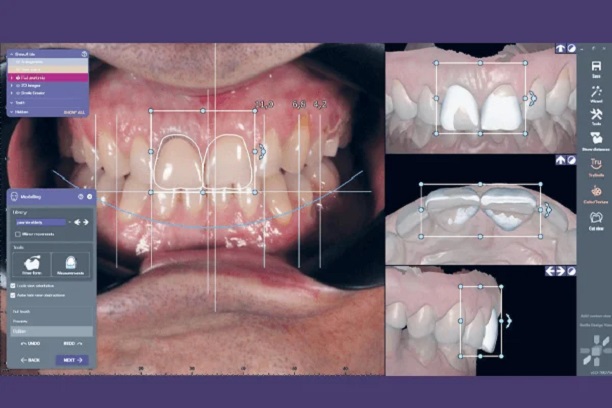

Através de fotografias e software especializado, projetamos como ficará o novo sorriso antes de iniciar o procedimento.

Software avançado que permite projetar e visualizar os resultados estéticos antes de iniciar o tratamento.